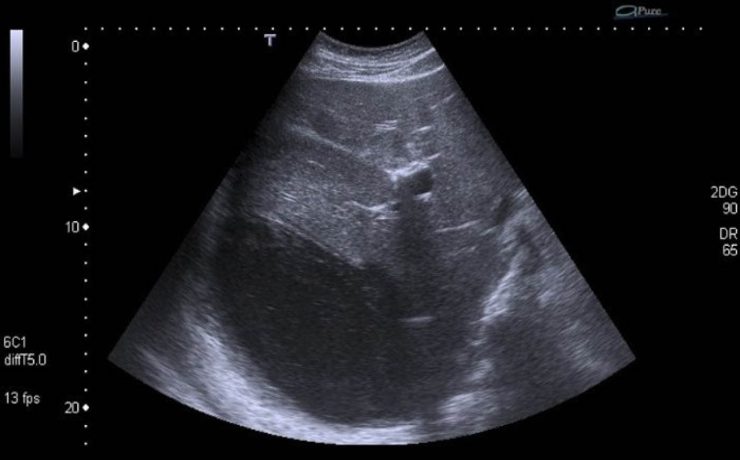

APENDICITIS DURANTE EL EMBARAZO

La apendicitis aguda durante el embarazo constituye la causa más frecuente de abdomen agudo quirúrgico no obstétrico, reportándose a nivel mundial una incidencia de 0.1 a 1.4 casos por cada 1,000 embarazadas. Algunos estudios en América Latina han reportado una incidencia aproximada de 1 por cada 1,200 embarazos. El diagnóstico